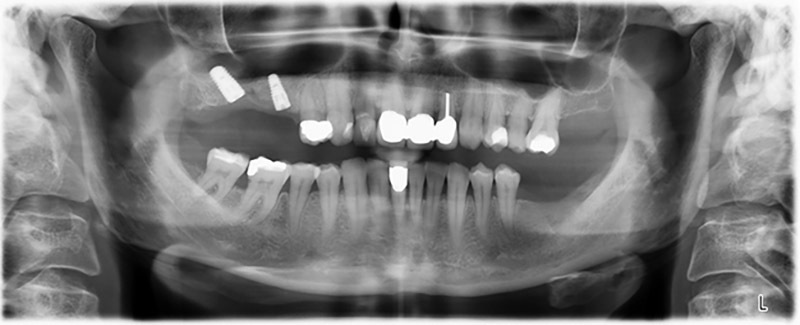

Al fine di pianificare e minimizzare i rischi, circa sei mesi dopo l'estrazione dei denti 16 e 14 viene effettuata una tomografia digitale volumetrica (DVT, Planmeca), la quale conferma chiaramente la mancata rigenerazione ossea nel volume desiderato (da fig. 2 a 7).

È necessario un rialzo del pavimento sinusale nelle regioni 16 e 14 per garantire una solida ricostruzione basata su almeno due impianti. Si auspica un accrescimento osseo su scala relativamente ampia a causa del volume osseo residuo estremamente ridotto in questo caso. Le principali procedure di accrescimento osseo sono invasive e incrementano il tasso di morbilità dei pazienti, oltre a essere costose in termini di tempo e denaro. Prevedere l'esito del trattamento diventa più difficile e il rischio di insuccesso aumenta. Il dentista informa la paziente e le propone una soluzione asportabile, fermamente rifiutata.

Per ridurre l'accrescimento nella regione 14, con il consenso della paziente si opta per il posizionamento e l'inclinazione dell'impianto 16 in direzione dorso-craniale (fig. 8).